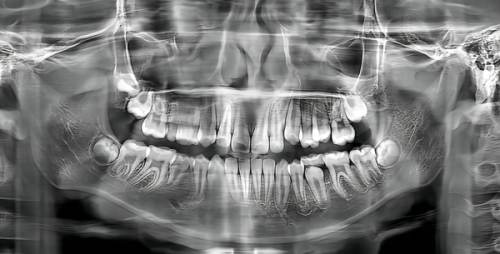

上海丁士德口腔诊所拥有一支专精的医疗团队。医生们都具备丰富的临床经验和专精知识,他们毕业于有名口腔院校,并且在各类口腔疾病的诊断和治疗上有着独特的见解和方法。无论是常见的牙齿矫正、补牙,还是复杂的种植牙手术,医生们都能游刃有余地应对。患者再也不用担心遇到技术不过关的医生,导致治疗成效不佳,从而加重牙齿问题带来的焦虑。